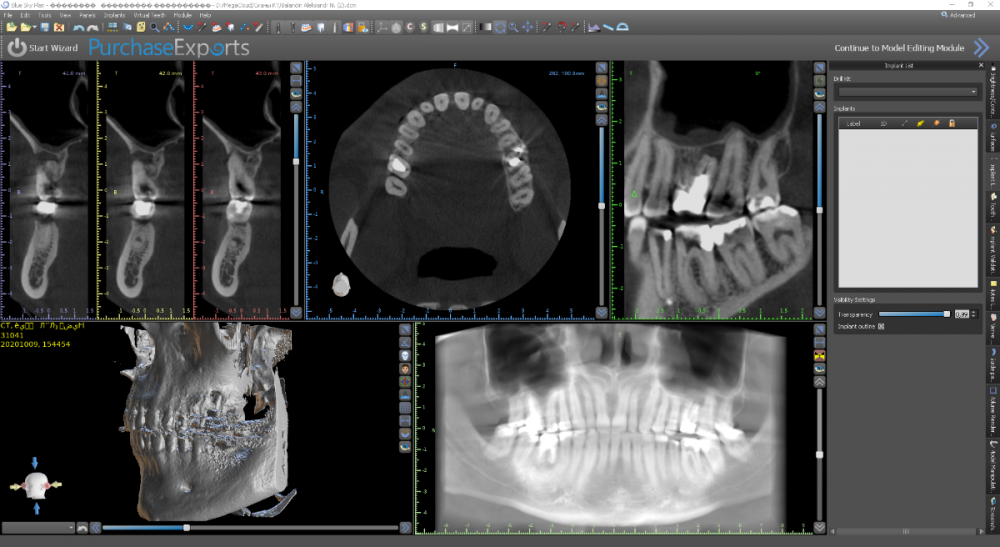

Женька Опубликовано 9 октября, 2021 Поделиться Опубликовано 9 октября, 2021 Коллеги здравствуйте. Планирую имплантацию, с синусом небольшим. Из анамнеза: зуб 2.6 ранее лечён в другой клинике. Попробовали перелечить и понаблюдать. Спустя полгода наблюдений вновь открылся свищевой ход. Приняли решение зуб удалять с последующей имплантацией. Собственно срок подошёл. Но на КТ дефект в области вестибулярной пластинки в проекции 2.7 никуда не делся (с чего бы). Отсюда вопрос. Раз уж всё равно будет разрез-лоскут-мягкие ткани. Стоит ли залезть и в эту область? Кмк может случиться швах с мягкими тканями из-за этого дефекта. Если уж залезать, то что делать? Убрать грануляции, обработать АБ+лидоксор, заполировать и ушить? Снимки до удаления и планирование. Разница 8 месяцев. Ссылка на комментарий

Женька Опубликовано 14 ноября, 2021 Автор Поделиться Опубликовано 14 ноября, 2021 Какой-то чудной зсл у меня получился... но это от недостатка опыта 100%. В общем фото сделал всего 2шт , скину в понедельник. Итак про ЗСЛ. Мой протокол: разрез, скелетирование, подшиваю лоскут для лучшей визуализации, далее пилотное дентиум не доходя 1-1.5мм, далее расширяю отверстие до нужного размера (здесь 3.8 имплантиум) и потом беру остеотом того же размера и стучим до появления "тупого" звука или ощущения "проваливания". Остеотомы у меня китайские, но со стоперами. Начинаю стучать и почти сразу чувствую, что провалился. Зондирую "зонтиком" - никакой эластичной подвижности... стучу ещё, тоже самое. Заметил, что стопер упирается проксимально в 2.7. Выкручиваю стоперы совсем. Стучу, звук особенно не меняется, но пациент отмечает неприятные ощущения. По остеотому 8мм (нативной кости 7 с копейками). Снова зондирую, снова не чувствую мембраны , пациент же говорит, что что-то есть, двигается будто. Решив, что хватит мучать бедолагу нарезаю пару столбиков Белкозина и пакую с помощью остеотома. Инсталирую имплантат и пациент отмечает чрезмерное распирание и легкую болезненность (еще 1.5 мм имплантата не погружено). Продолжаю глубить, всё спокойно. В итоге остановился на 1.5мм заглублении и заглушке, не рискнул ставить фдм, торк около 10). Вырезал сст, подшил вестибулярно и наконец-то закончил. Судя по РГ я подломил не только кортикальную пластинку, но и приличный кусок губки? Критично ли? После отметил лёгкую заложенность носа, без геморрагий. 4 Ссылка на комментарий